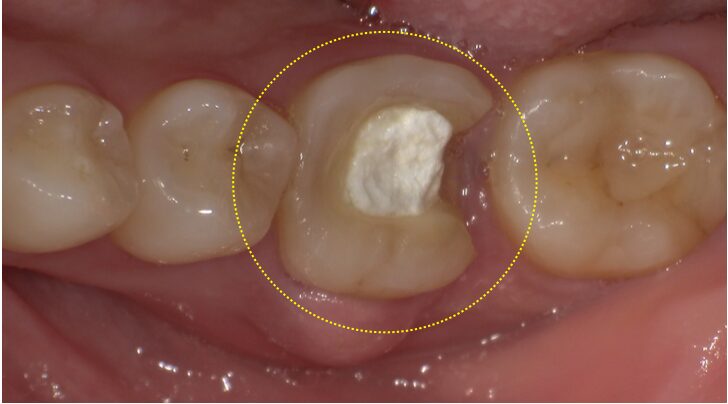

治療前の状態 歯根破折により歯ぐきが腫れている

治療前の状態 保存困難と判断

| 診断名・症状 | 歯根破折 歯ぐきが腫れている |

| 治療内容 | 歯ぐきが腫れてきたことを主訴に、かかりつけ医に相談したところ、根っこに問題があると言われた。かかりつけ医では治療は困難だと言われ、根管治療専門医を紹介してもらったとのことで、根管治療専門医で精密検査を行ったところ、歯根破折が見つかり、保存が困難だと診断された。 患者さんの年齢は30代と若く、抜歯後の治療に関して、ブリッジ治療にするかインプラント治療にするかで悩んでいた。 ブリッジ治療では、天然歯を大きく削る必要があり、できるだけ綺麗な歯を削りたくないとの希望でインプラント治療を選択された。 しかし、インプラント治療においても不安要素があり、なかなか治療に踏み込めなかった。 インプラント治療における不安要素として、 ・痛みや腫れが怖い ・小さい子供もいるので、治療期間が長くなるのが困る ・治療後のインプラントのメンテナンスが不安 などが、あげられた。 CT撮影による精密検査を行うと、歯根破折による炎症はあるものの、抜歯する歯周囲の骨は十分に存在しており、抜歯即時インプラント手術が適応できると判断しました。 抜歯即時インプラント治療では、患者さんが抱えている不安を全て解決できる可能性が高く、患者さんに説明したところ、この方法であれば、「是非インプラントをやってみたい。」と、納得された様子で、前向きに治療と臨んでいくことができたとのことです。 ①抜歯+インプラント埋入+骨の再生治療 抜歯の際には、周囲の骨へのダメージを最小限にするために、丁寧な抜歯を行います。 抜歯後すぐにインプラントを埋入していきますが、天然歯の奥歯とインプラント(根の形態・直径)には大きな違いがあり、抜歯した穴の大きさとインプラントにはギャップが生じるため、そのギャップには骨補填材を填入し、骨の再生も同時に促します。 たった1度の外科処置で、この3つの治療を同時に行うので、患者さんの負担は最小限で済みます。 さらに、メスによる切開、糸による縫合なども行わないので、術後の腫れが極端に少なくで済みます。 私の経験上、ほぼ痛みが出ること、腫れることはありません。 当日は、ヒーリングキャップ(白色)を装着するため、術部に食べ物や汚れが入り込むこともありません。 ②仮歯の型取り 術後3~4ヶ月後に仮歯の型取りを行います。 一度、仮歯で噛み心地や見た目、お掃除のしやすさなどを確認し、問題がなければ、 その仮歯の形を参考に、最終的なセラミックの歯を製作していきます。 ③最終上部構造完成 処置開始時から約4~6ヶ月で最終のセラミックの歯が完成します。